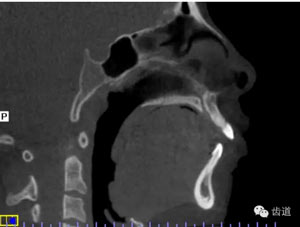

治療后氣道截圖(CBCT)